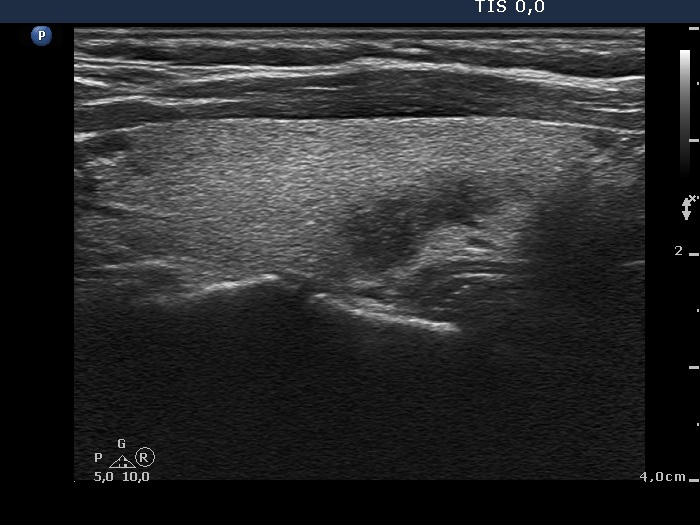

Initial examination (first row of images):

Clinical presentation: A 39-year-old woman was referred for evaluation of neck complaints lasting for more than a month. The patient had fever, neck pain. She has got two courses of antibiotics and non-steroid anti inflammatory drugs which had no effect.

Palpation: The right lobe was painful and hard while the left lobe was tender.

Laboratory examination: TSH 0.01 mIU/L, FT4 29.1 pM/L, FT3 7.45 pM/L, CRP 31.2 mg/L.

Ultrasonography: The thyroid presented with hypoechoic areas which had blurred borders. The echogenicity index was approximately 65% in the right and 20% in the left lobe. The thyroid was almost completely avascular.

Diagnosis: subacute, granulomatous de Quervain's thyroiditis.

Suggestion. Steroid therapy was suggested.